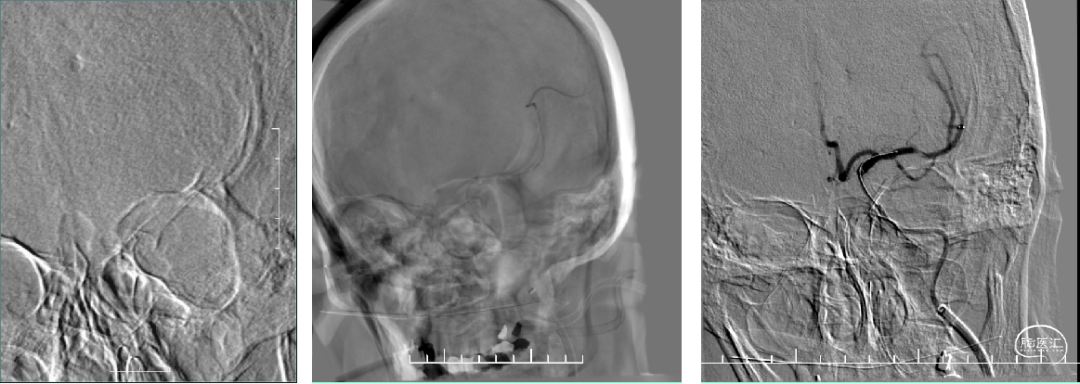

术后正侧位—TICI 3级

本病例为老年女性急性L-MCA血管闭塞,最常见的病因为栓塞或动脉粥样硬化基础上急性血栓形成(ICAS),因为颅内动脉夹层发生率较低为(3.6~4.4)/10万,且为青年卒中的重要病因,因此,我们在取栓过程中,首先采用了抽拉结合技术,但未达到有效开通。通过影像和操作过程观察,考虑局部病变可能为左侧大脑中动脉夹层的导致急性闭塞,重新调整手术方案,全麻后行左侧大脑中动脉支架置入术,夹层成型满意,患者术后恢复良好。

由于颅内动脉夹层发病早期临床症状缺乏特异性,容易导致诊断延迟乃至漏诊误诊。颅内动脉夹层致残性高,技术要求较高。我们这个病例就是一例左侧大脑中动脉M1急性闭塞,在治疗过程中证实为夹层,运用球囊联合中间导管技术成功血管开通、支架置入血管成型满意。此技术也是急诊处理复杂急性血管闭塞(栓塞、ICAS、夹层、其他原因)比较稳妥、安全、有效的办法。

兼顾三种可能的情况,审慎考虑下一步手术策略,我们采用球囊扩张+中间导管同轴的方式,即在球囊扩张后,中间导管在同轴下安全跨过病变段血管,这样既可以扩张病变管腔,也可以以最安全的方式释放支架,获得成功开通,同时避免反复取栓操作造成的血管壁损伤或血栓逃逸。

从手术后血管造影来看,这例患者符合夹层的诊断。有人可能会提出,既然判断为夹层,为何不直接覆盖支架?其实这也是一种选择,但如果夹层的血管壁内有血栓,释放支架过程则有可能会导致血栓逃逸,而我们采取的球囊+中间导管同轴技术则可以有效避免这一风险,提高安全性。